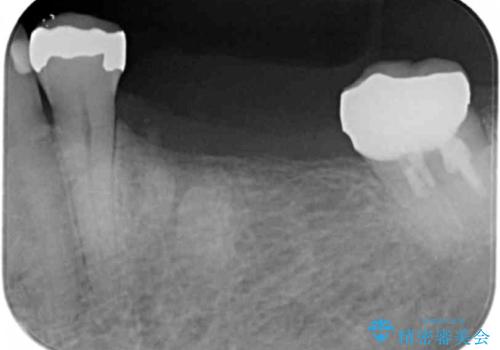

- 歯を喪失してしまい、咬合機能の回復を求めて来院されました。

入れ歯ではなく、よりしっかりと噛めるようになるインプラント治療を希望されましたが、将来的な安定を見込むにはインプラント周囲の骨量が少ない状況でした。

舌側にある大きな骨隆起を除去するとともに、除去した骨と人工骨を用いてインプラント周囲の骨を造成します。

自家骨と人工骨による骨造成は、長期的に見て安定し吸収が少ないとされる骨の造成法です。

インプラント周囲に、必要十分な骨を作ることが長期渡りインプラントにトラブルを起こしにくい鍵となります。